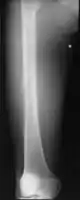

Medical imaging usually shows a well-defined wide-based bony growth on the surface of bone.[5] It can be pedunculated and irregular, giving it a "bizarre" appearance, and is not connected to underlying bone.[2]

X-ray hand, BPOP 2nd metacarpal

X-ray hand, BPOP 2nd metacarpal (side view)